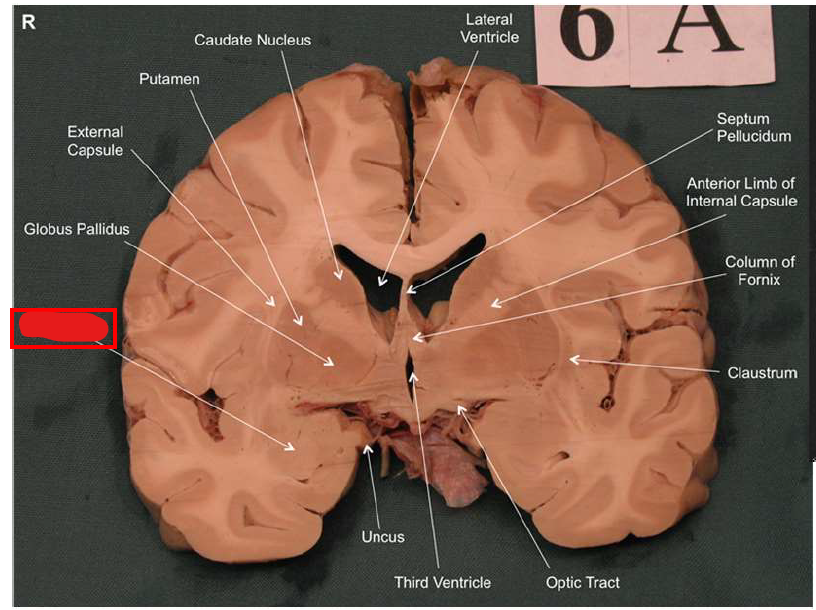

What is the function of the amygdala?

Emotions & Memory Hub

Processes emotions (esp. fear & pleasure)

Helps us remember emotional experiences

Imagine the amygdala as a fire alarm in your brain. When it senses danger (fire!), it triggers the alarm (fight-or-flight response) almost instantaneously and remembers the event vividly (emotional memory)